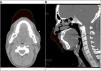

A health-worker's CT scan showing the air space between the mask (3M Aura 1870+) and the face skin (138mL). This volume remains relatively constant throughout the respiratory cycle, since its shape and material confers certain rigidity (fig. 1). Dead space of the respiratory airways is increased by about 50–80%, compensated with a raise in pulmonary ventilation to keep alveolar ventilation and CO2 stable1. This could have an impact in severely impaired respiratory patients.

Fig. 1